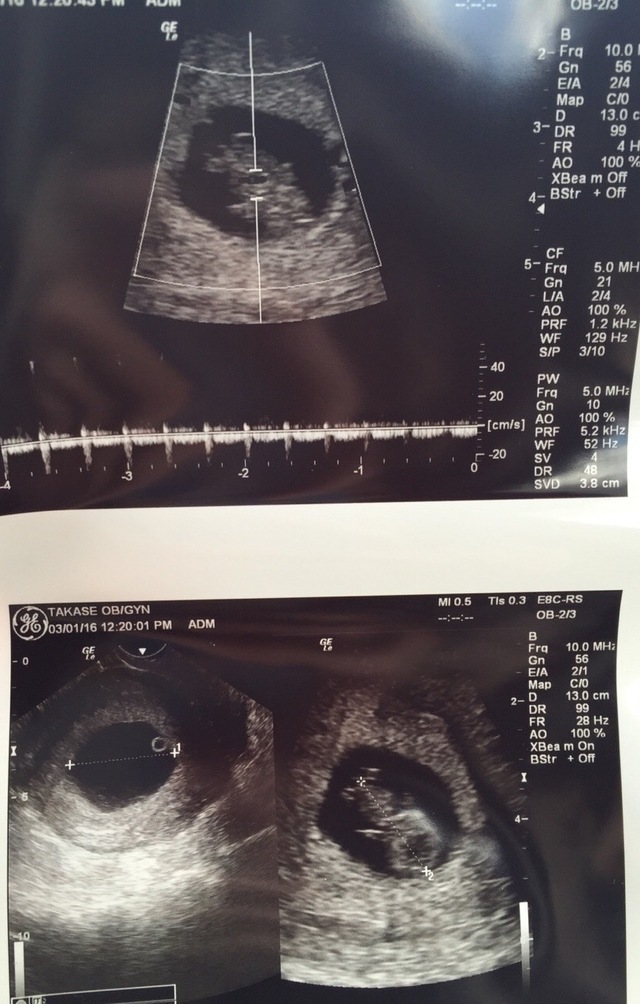

8週0日(8w0d・性別不明)|まなん(´ω`) さん(35歳)

エコー写真撮影時のエピソード:生活面ではニオイでの悪心増悪があり、食事も酸っぱいものを求めるようになったことや長男妊娠中と同じく強い立ちくらみもあり、妊娠かな?と受診したら8週目でした。絨毛膜下血腫があり、自然消失を待ってる状態です。胎児ちゃん自体はエコーで心拍も確認でき、元気な様子でした。このまま大きくなってねと祈りながらエコー映像を見てます。